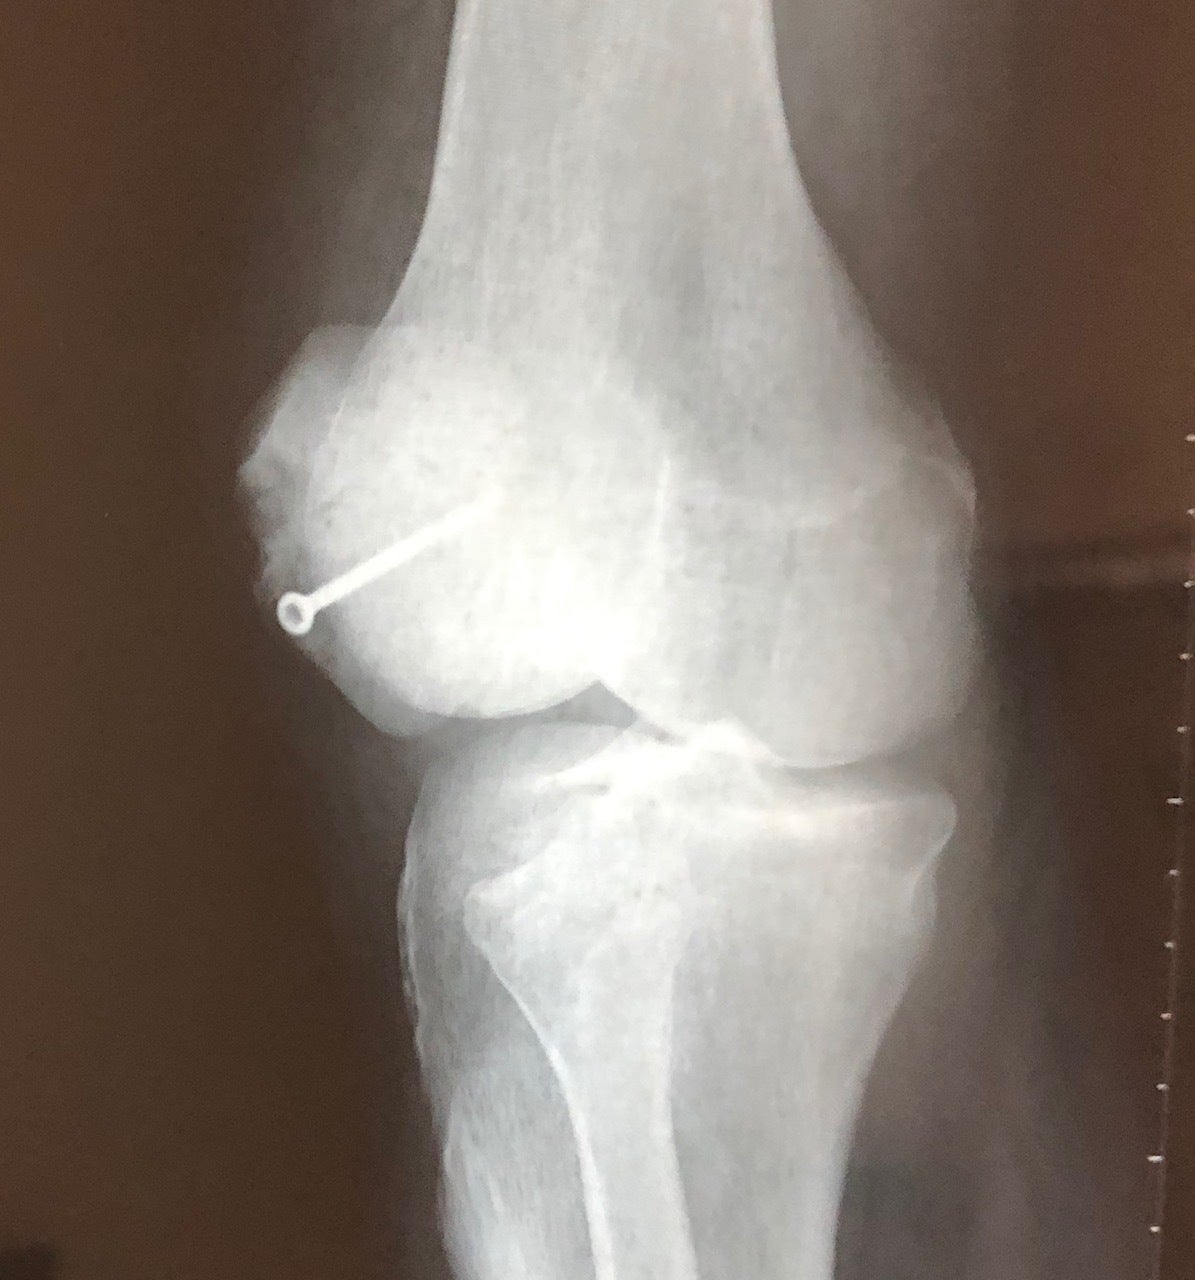

写真でご覧のとおり、見るからに元気ではあるのですが、実はぼくの身体は大動脈が人工血管になり、右足の大腿骨と膝は数本のボルトで繋がれています。

そのため思うように身体を動かすことができません。

(以下、レントゲンや縫合後のお見苦しい画像がありますがご容赦ください)。

手術による胸部切開痕は、24時間絶えず痛みが消えることはなく、時折り激痛で立っていられないほど呼吸が苦しくなることもあります。

ウォーキングは出来るけど、重い物を持って歩いたり5キロぐらい歩くと膝が腫れて悲鳴を上げてしまいます。しゃがんだり正座することも困難です。

トレーニングしようにも思うようにできません。無理して人工血管や右足のボルトに負担がかかるかと思うと怖くて運動ができませんでした。